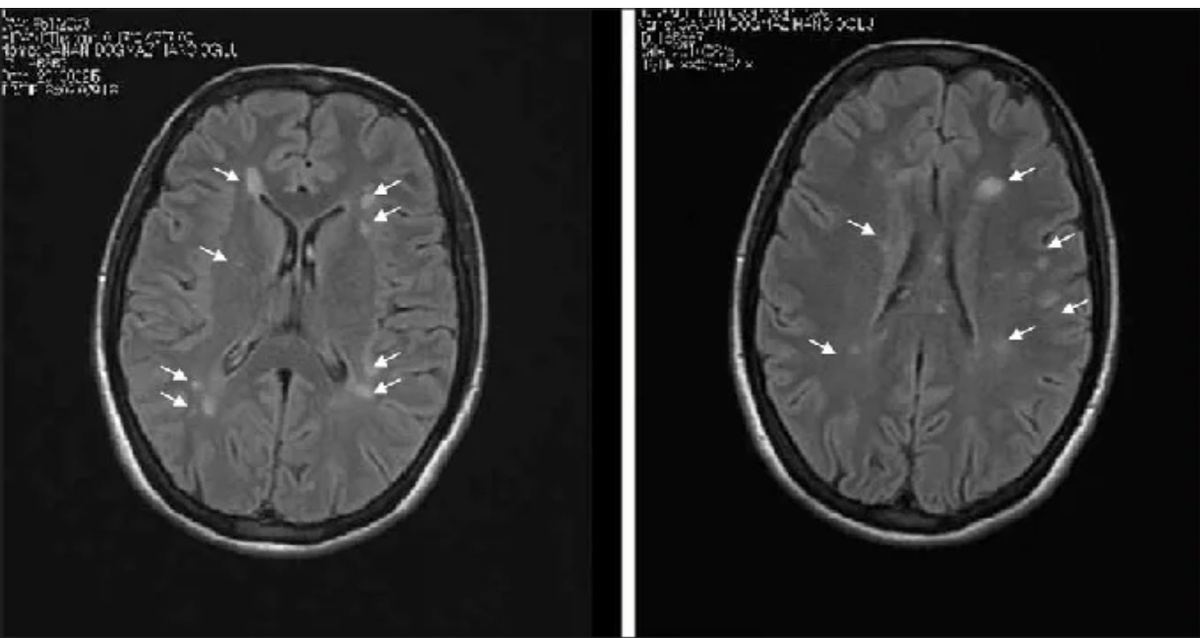

Примеры из практики:

У мужчины 65 лет после перенесённых инсультов видны очаги нарушенного кровообращения. Позднее они трансформируются в кистозно-глиозные изменения.

Множественные очаги глиоза свидетельствуют о ранее перенесённых нарушениях мозгового кровообращения, но меньшего масштаба.